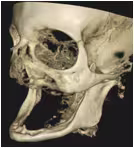

Advanced Full-Arch Reconstruction for the Severely Edentulous

Join Dr. Michael A. Pikos March 20-21, 2026 for his signature Subperiosteal Implant Course inspired by his 35,000 cases of Advanced Full-Arch Treatment, and being the last resort to helping patients when Traditional Implants Are No Longer Viable.